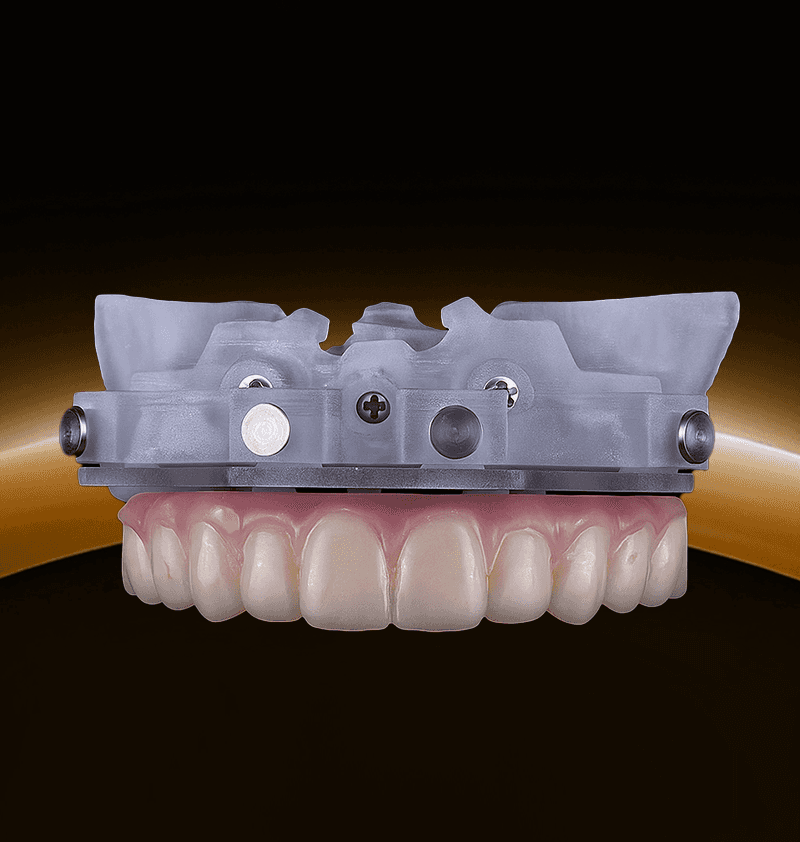

Seamless digital solutions for every step of the implant journey.

From scan to final delivery, 3Sixty streamlines your workflow with smart planning, precision guides, and real clinical support.

3Sixty is a digital dental lab with 150+ dental and technical experts supporting every case. From treatment planning to surgical guides and full-arch workflows like our groundbreaking Anatomic Guide®, we help streamline complex procedures. Trusted by over 3,000 dentists, we make digital implant dentistry simpler, faster, and more predictable.

"What I can appreciate about the [Anatomic Guide®] is that it will save you time and also will give you better guidance when placing the implants."